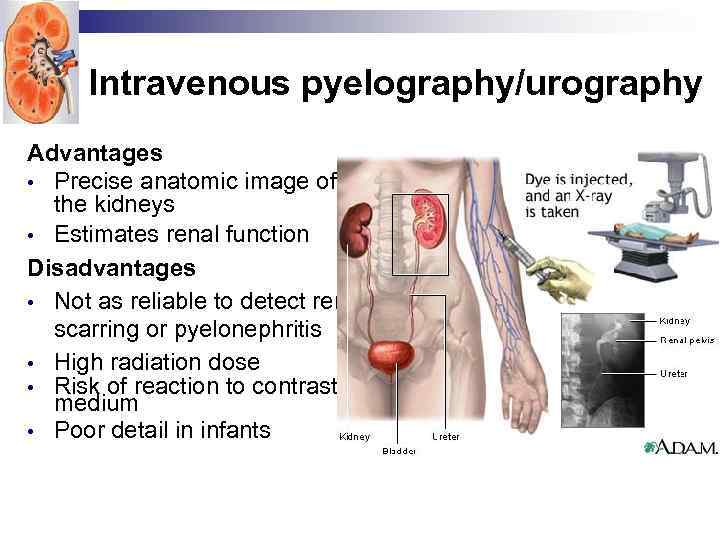

Intravenous pyelography/urography Advantages • Precise anatomic image of the kidneys • Estimates renal function Disadvantages • Not as reliable to detect renal scarring or pyelonephritis • High radiation dose • Risk of reaction to contrast medium • Poor detail in infants

Intravenous pyelography/urography Advantages • Precise anatomic image of the kidneys • Estimates renal function Disadvantages • Not as reliable to detect renal scarring or pyelonephritis • High radiation dose • Risk of reaction to contrast medium • Poor detail in infants